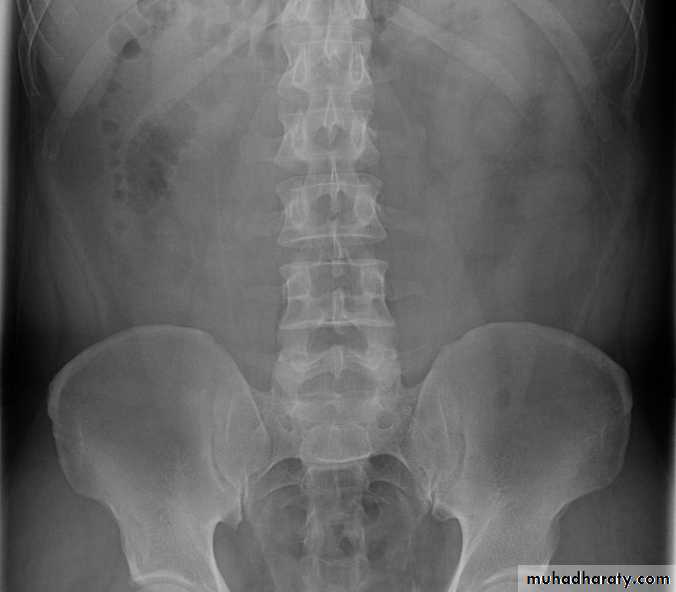

-Over 90% of calculi are radiopaque on plain films and virtually all on CT as very sensitive for detection of calculi, even those that appear radiolucent on plain film.

-Plain film may be useful in demonstrating calculi.

• Ddgx of stone on KUB :

• 1. Gall stone

• 2. calfied LN , cartilage ,fibroid,

• 3. Phlebolith: round, lucent centre.